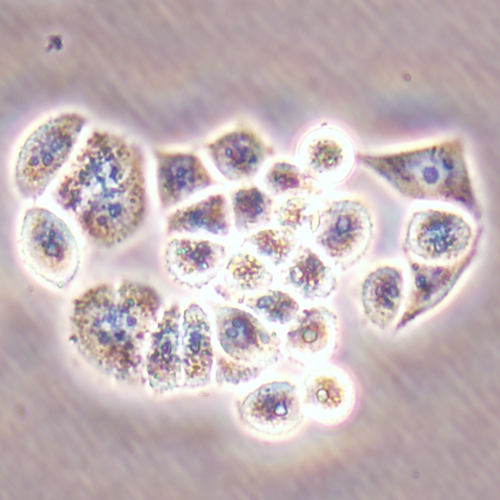

Before the advances in deep learning, the traditional approach for cell detection/segmentation is to employ low-level handcrafted features, reflecting color, edge, and shape characteristics of cells. This approach has given promising results when the features are defined properly, as a good representation of the visual cell characteristics. On the other hand, these characteristics may change from one cell type to another (see Fig. 1) and new features need to be defined to meet the cell characteristics of a new type. Additionally, when there exists heterogeneity in the visual characteristics of the same cell type, using a single model may not be sufficient to detect all cells of this type, particularly for cancer cells which are exploited more in high throughput screening.

We test our DeepDistance model on three datasets, each of which consists of live cell images of a different cell line. They are the CAMA-1, MDA-MB-453, and MDA-MB-468 human breast cancer cell lines. The images in all datasets were acquired at magnification and pixel resolution. An example image from each dataset is shown in Fig. 1. As seen in this figure, cells might be visually different within and across different cell lines.